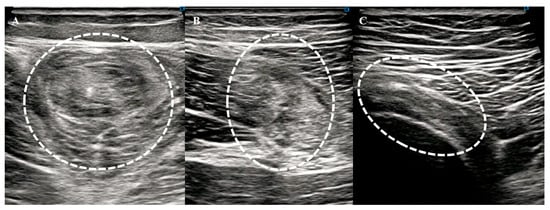

2.3. Hamstring Muscle Diagnosis Using US

- Changes in echogenicity or fiber disruption within the muscle.

- Edema or hemorrhage, defined as areas of increased echogenicity with or without visible fiber disruption in orthogonal planes.

- Hypoechoic fluid tracking along the fascial layer surrounding the muscle was indicative of intermuscular hematoma.